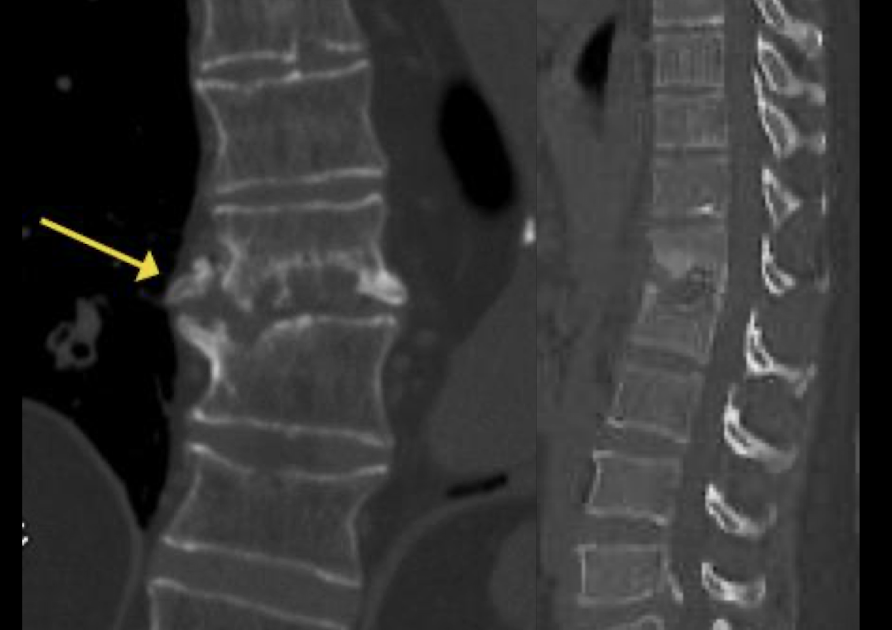

Tc

poco util, perdida de la morfología vertebral

iregularidad plataformas